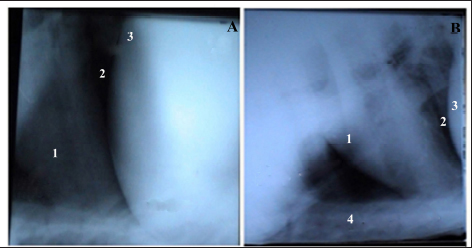

Radiography showed that the reticulum in healthy buffaloes was radio-opaque and free from any metal bodies. The reticulum and heart were radio-opaque structures, and the diaphragm was visualized as a prominent black line separating them. Adhesions between the heart and diaphragm or between the reticulum and diaphragm were not seen. The heart, as was a radio-opaque structure, had clear borders and a regular size and shape (Fig. 1a and b).

Radiography in healthy buffaloes revealed an empty reticulum, a well-defined diaphragm, and a normal heart with a radio-opaque appearance. Braun et al. (1993) discussed the benefit of radiography in the diagnosis of TRP in cattle. At the same time, Braun et al. (1994) and Khalphallah et al. (2015, 2016c, 2016e, 2017) reported the diagnostic importance of ultrasonography and radiography in buffaloes and cows with TRP and/or TP.

Fig. 1. Lateral radiographic view of the cranial abdomen (a) and the thorax (b) of a 3-year non-pregnant female buffalo showed the normal radiographic appearance of the reticulum, heart, and diaphragm. 1; Heart. 2; Diaphragm. 3; Reticulum. 4; Sternum.